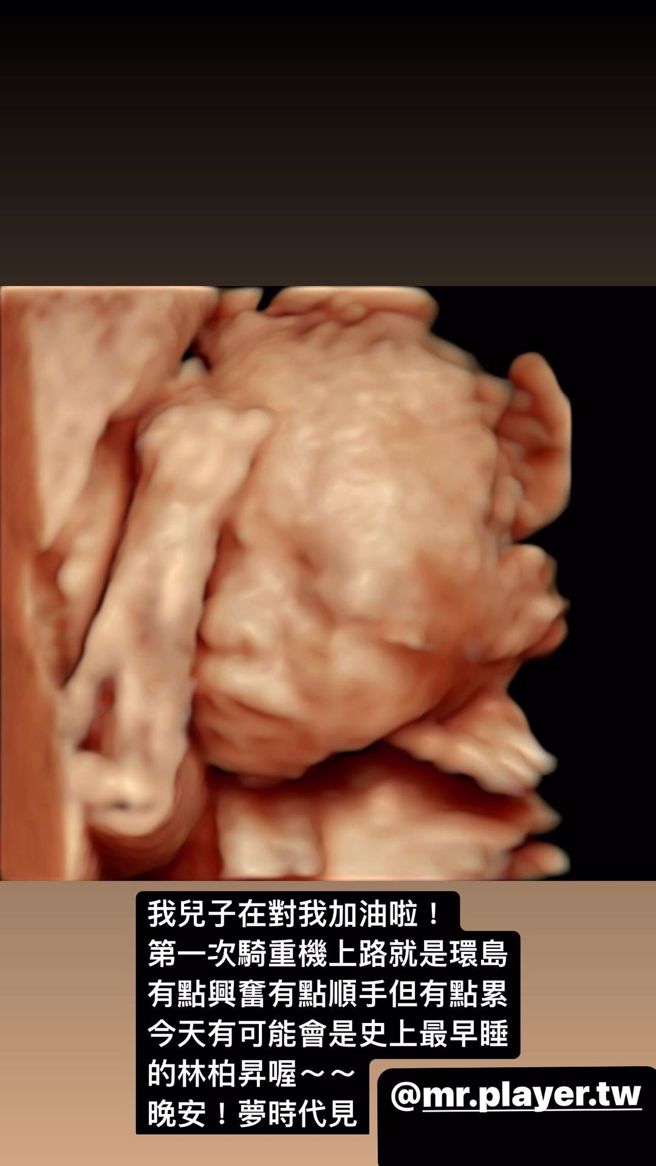

KID林柏升7月时才公开老婆「东区妹仔」Rita怀孕,9月16日就公布宝宝的性别是男性,吸引粉丝献上祝福,而升格人父后的KID,不时就在IG化身「晒娃魔人」,日前便晒出爱妻产检的超音波照,不仅宝宝五官轮廓已经成形,当他看见儿子握住小拳的举动,更幸福甜喊:「我儿子在对我加油啦!」

KID在24日在IG限时公开婴儿的超音波照,可见到胎儿眼睛、鼻子及嘴巴等五官皆已逐渐长成,儘管尚看不出小孩长得像爸爸或妈妈,然而又一条新生命的诞生总令观眾激动不已。更令人注意的是,KID儿子举手握拳的姿势,让初当爹的KID融化直喊:「我儿子在对我加油啦!」藏不住满满的父爱。

林柏升IG看见儿子超音波照握拳,让他难掩做父亲的兴奋。(图/林柏升 IG)

KID坦言,近日是为了庆祝《综艺玩很大》八周年,首次重机上路便是环岛之旅,儘管让他很兴奋却有点疲累,打趣说道「今天有可能是史上最早睡的林柏升喔」,就算是这样,好不容易喜获麟儿的KID,看见儿子小手握拳的模样,彷佛全身充完电般,身体又有动力持续向前。